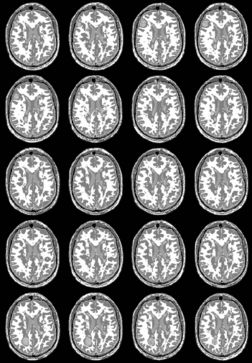

| + | {| | ||

| + | |+ '''Fig 3. MS Longitudinal Study (1995)''' | ||

| + | |valign="top"|[[Image:seven.jpg|thumb|252px|longituidinal MS, one subect, segmentaiton result without EM]] | ||

| + | |valign="top"|[[Image:eight.jpg|thumb|252px|Results with EM]] | ||

| + | |} | ||

The EM segmener was the first algorithm that could produce high quality segmentations of white matter and gray matter from MRI, with no manual intervention needed on a per case basis. This proved to be very valuable in a large longitudinal study of MS in the period 1994 - 1995.